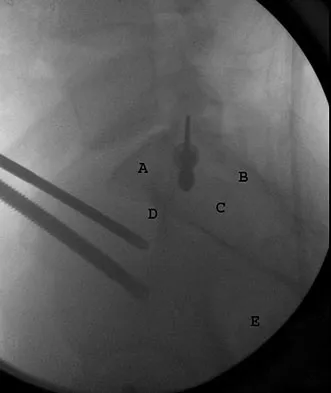

An otherwise healthy 37-year-old man fell off the flatbed of a delivery truck and landed directly on his dominant left hand. Surgical stabilization of a distal radius fracture is performed. An intraoperative radiograph is shown in Figure 22. What is the next most appropriate step in management?